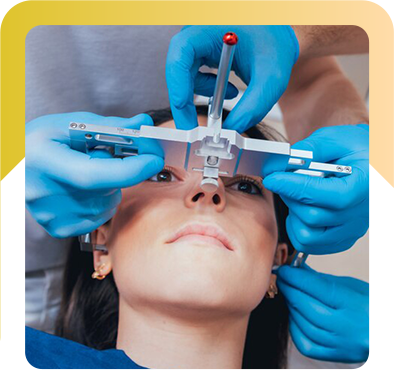

What Does Rhinoplasty Do?

Corrects Cosmetic Issues:

- Bulbous Tip: Reshapes a large, round, or poorly defined nasal tip.

- Upturned Nose: Adjusts an overly upturned nose or visible nostrils.

- Hooked Nose: Straightens a downward-curving nose.

- Droopy Nose: Lifts the nasal tip to eliminate a droopy look.

- Wide or Small Nostrils: Adjusts nostril size for better proportion.

- Nasal Bridge Irregularities: Smooths dips, bumps, or irregularities.

Corrects Structural and Functional Issues:

- Deviated Septum: Improves breathing by correcting a deviated septum.

- Facial Balance: Adjusts nose size to enhance facial symmetry.

- Blocked Nasal Passages: Opens obstructed nasal passages for easier breathing.

- Physical Examination – The surgeon assesses facial structure, nasal interior, and breathing function, especially for conditions like a deviated septum.